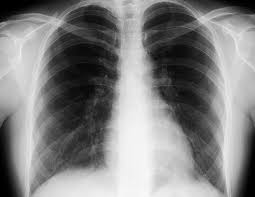

胸部X線

肺に影が写った場合。再検査ではCTなど精密画像検査。

当院では胸部X線画像病変検出ソフトウェア (CXR-AID)を使用しており、医師とAIによるダブルチェックを全症例に行っております。

- 胸部X線異常(肺の影など) → 急ぎで精密検査